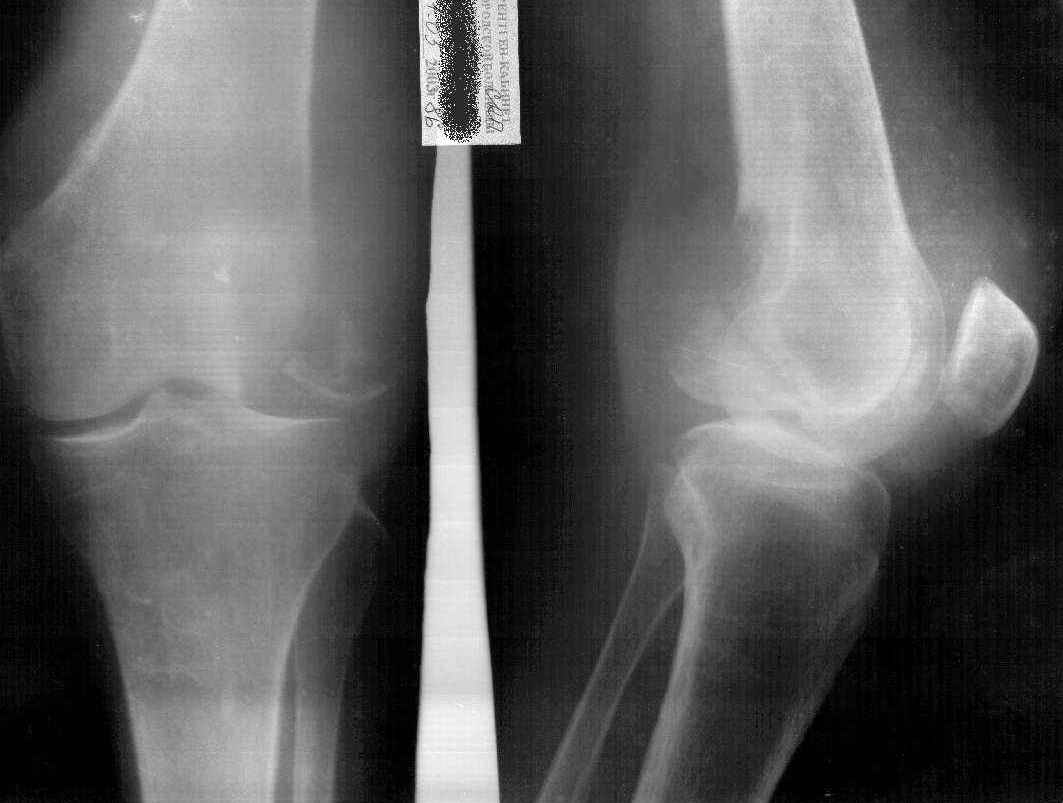

Больная К.85 лет, получила незначительную травму в конце июля 2002 года (рентгенограммы от 26.07.2002). Ушиб коленного сустава, отека не было, гемартроза не было. Лечилась местными средствами, троксевазиновая мазь, водочные компрессы. В дальнейшем развился посттравматический периартрит правого коленного сустава, синовиит правого коленного сустава. Больная на дом приглашала много различных врачей, из санаторной сети, частных хирургов, из скудных полученных данных возможно было выяснить, что получала диклофенак-натрий внутримышечно, примерно 10 раз. Несколько внутрисуставных инъекций, сколько и с каким промежутком выяснить не удалось, но более менее достоверно, что один раз вводили гидрокортизон и один раз кеналог-40. Записи практически никто не оставлял.На данный момент больная категорически отказывается от госпитализации в любое из предложенных отделений ни только для лечения, но и для обследования. Ищет врача, который назначит "правильную" мазь.Моя версия, асептический некроз наружного мыщелка правого бедра, после многократного введения гормональных противовоспалительных препаратов (рентгенограммы от 07.05.03).

AB> Моя версия, ассептический некроз наружного мыщелка правого бедра,

Многократного введения вроде и не было? Вообще, хрящевые язвы после десятков инъекций кеналога вполне ожидаемы, но тут такой остеолиз... На онкологию тоже не очень похоже... И на артрит не очень...

В возрасте 84 лет незначительная травма на фоне остеопороза могла послужить причиной перелома ( что возиожно и присутствует на предоставленных RTG

особо похоже на боковых), на этом фоне в результате блокад, пусть и не многочисленных, развился асептический некроз мыщелка бедра.

D-z:Старый несросшийся перелом наружного мыщелка правого бедра.Посттравматический ( ятрогенный?)

асептический некроз наружного мыщелка бедра.

Если верить клинике (отсутствие гемартроза) говорить о первичном переломе наружного мыщелка бедра нельзя. Да и не ходила бы больная с таким переломом. Плюс ко всему, практически, не бывает при данной локализации переломов без смещения.

Моё мнение: Асептический некроз наружного мыщелка бедра с патологическим переломом и рассасыванием приферического фрагмента.

Картина близкая к асептическому некрозу головки бедра при медиальном перломе шейки бедра - но в этом случае перелом первичен, а некроз вторичен.

Еслии верить многократному применению гормональных препаротов, то первичный (без травмы) асептичесий некроз имеет право быть. Даже не столько асептический некроз, сколько остеопоротическая резорбция костной ткани медикаментозного происхождения.